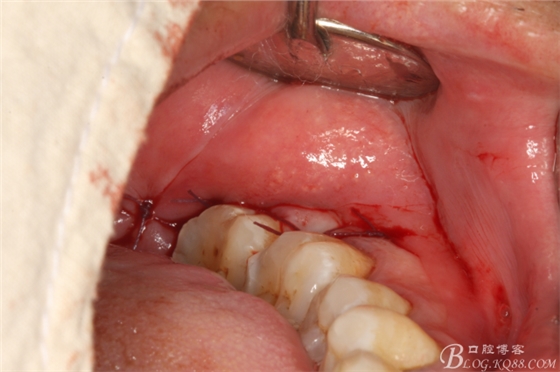

圖1. 口內(nèi)38完全埋伏

圖2.切開、翻瓣、去骨